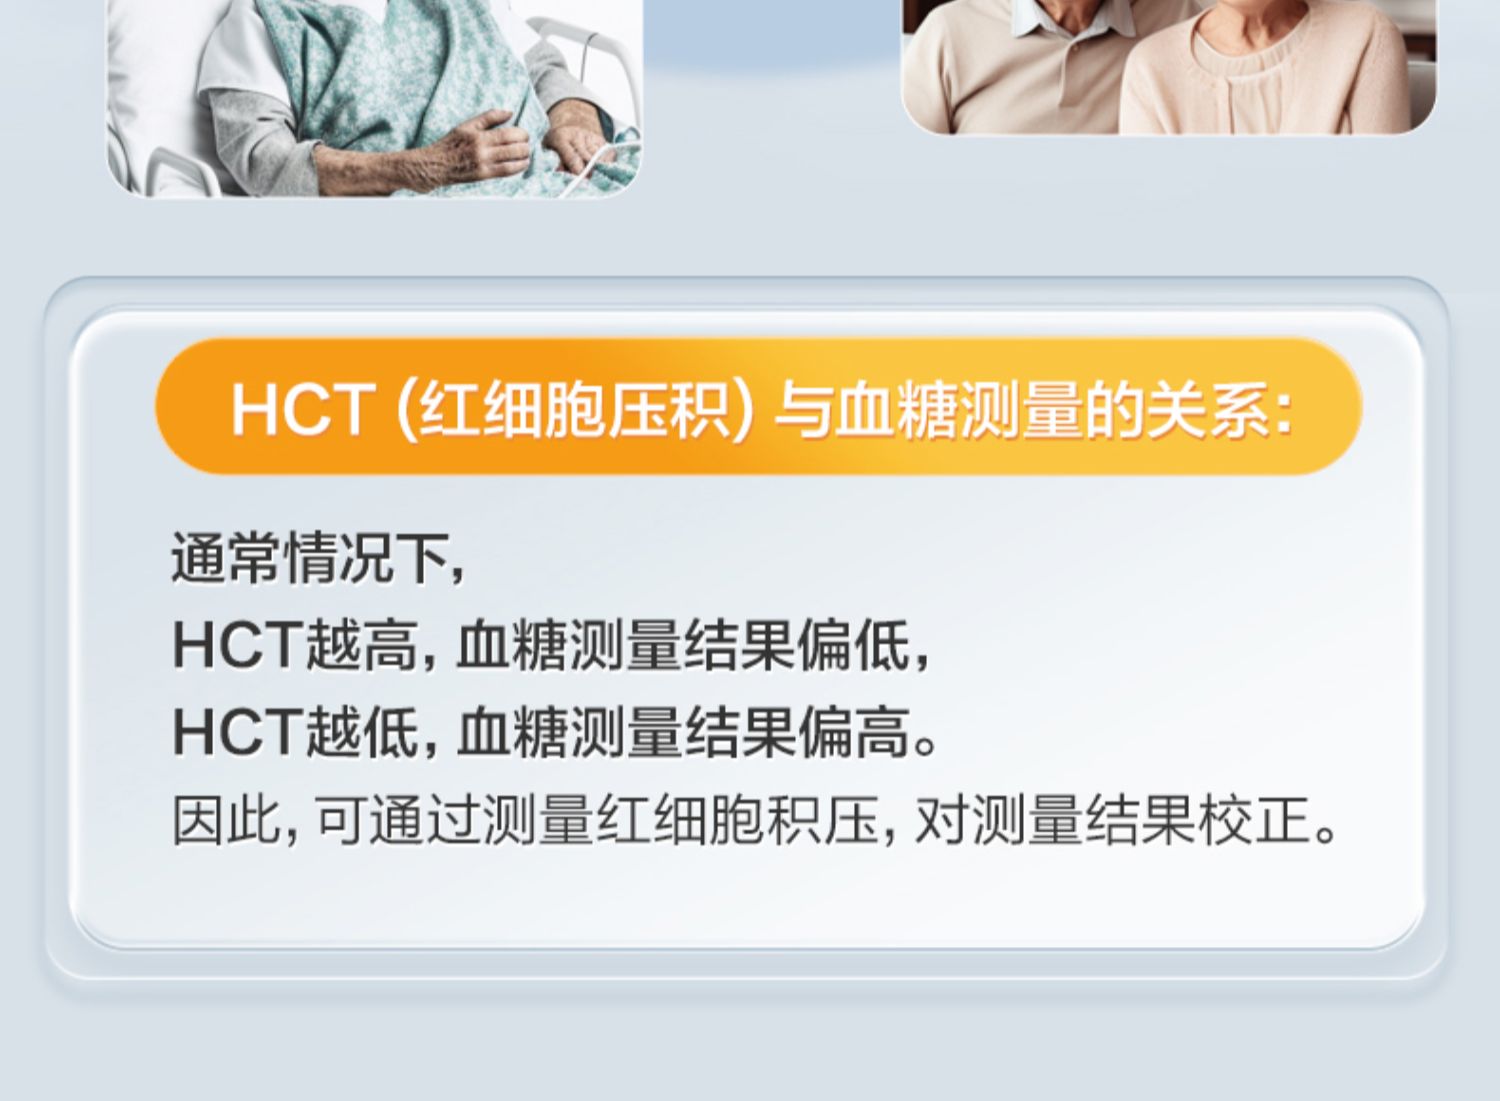

可孚新国标血糖测试仪家用测糖仪试纸官方旗舰店测血糖的仪器孕妇